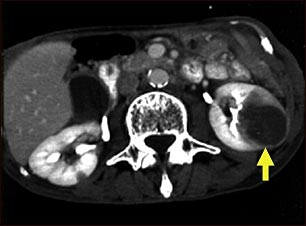

Metástasis del riñón - TC

TC del abdomen medio de un paciente con carcinoma pulmonar que muestra metástasis (cáncer diseminado) hacia el riñón izquierdo. Obsérvese el tumor del riñón, al lado derecho de la imagen, de forma circular, grande y oscuro.